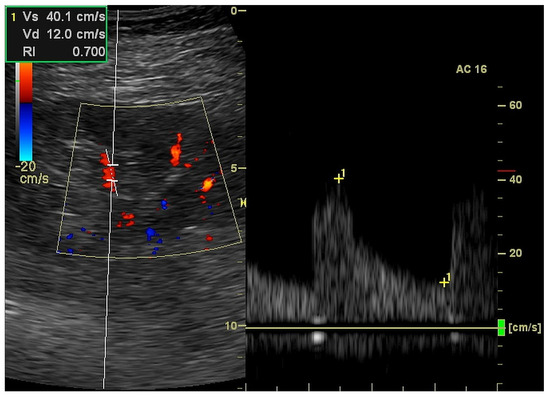

2.3. Kidney Ultrasound

| RI (ratio) | 0.701 | 0.115 | 0.721 | 0.169 |

| EDV (cm/s) | 13.6 | 5.6 | 12.2 | 9.7 |